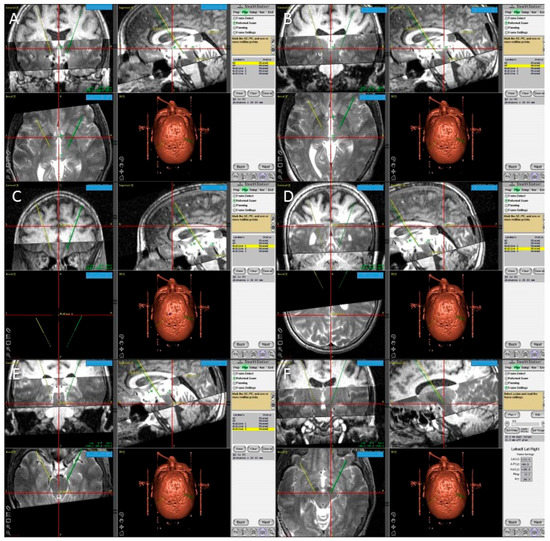

The second method we used to calculate the STN coordinates was direct visualization of the STN on a T2 weighted MRI (Figure 5) [55]. The STN is the almond-shaped hypointense structure located lateral and anterior to the red nucleus. We identified an axial T2 image that showed the largest red nuclei circumference, and then we drew a line from the midline, medial to lateral, along the anterior edge of RN. The center of the STN was chosen at the extension of this straight line about 12 mm from the midline. Then the coordinates were calculated using the same Excel worksheet. Another method of the STN coordinates localization was done in the OR, using the FrameLink software, which is a part of the StealthStation navigation system (Medtronic, Minneapolis, MN, USA) (Figure 6). The software compensates for head and frame tilt in any direction. It allows calculation of the STN coordinates and planning of suitable entry point and trajectory of the DBS electrode that avoid going through the cortical sulci, the ventricles, or any cerebral blood vessels. The final coordinates for the procedure were derived from all the previous techniques and subsequently adjusted using intraoperative electrical microrecording and macrostimulation.

Figure 6. Screen shots from the FrameLink software of the StealthStation showing fused T1 and T2 magnetic resonance imaging (MRI) images of the patient and the planning process with identification of the posterior edge of the anterior commissure (A); the anterior edge of the posterior commissure PC (B); three midline points (CE); and the final coordinates of the right subthalamic nucleus (F).